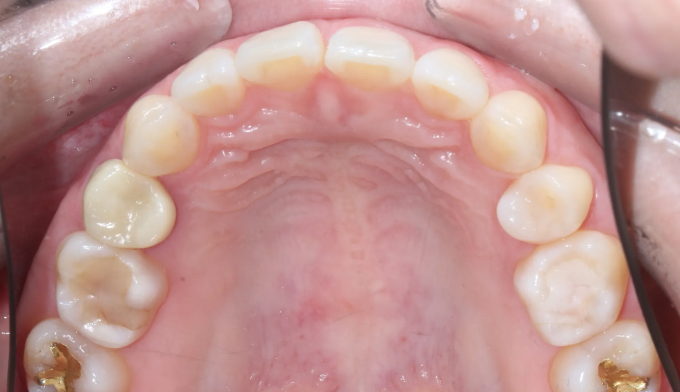

전에 교정치료를 마무리하고 지내던 중 치아 안쪽에 붙여놓은 유지장치가 떨어지면서 관리를 못하게 된 경우입니다. 이런 경우 앞니가 다시 틀어지거나 벌어질 수 있습니다.

위 유지장치는 모두 제거되어보이고, 아래 유지장치 또한 양 끝이 끊어져서 치아사이가 벌어져 보입니다.

서비스직에서 일하고 있어 치아 안쪽으로 붙이는 설측교정을 원하였고, 9개월만에 교정치료 종료 하였습니다.

유지장치가 떨어지면서 벌어진 치아들과 깊어진 앞니들을 이상적인 위치로 배열시켰습니다.